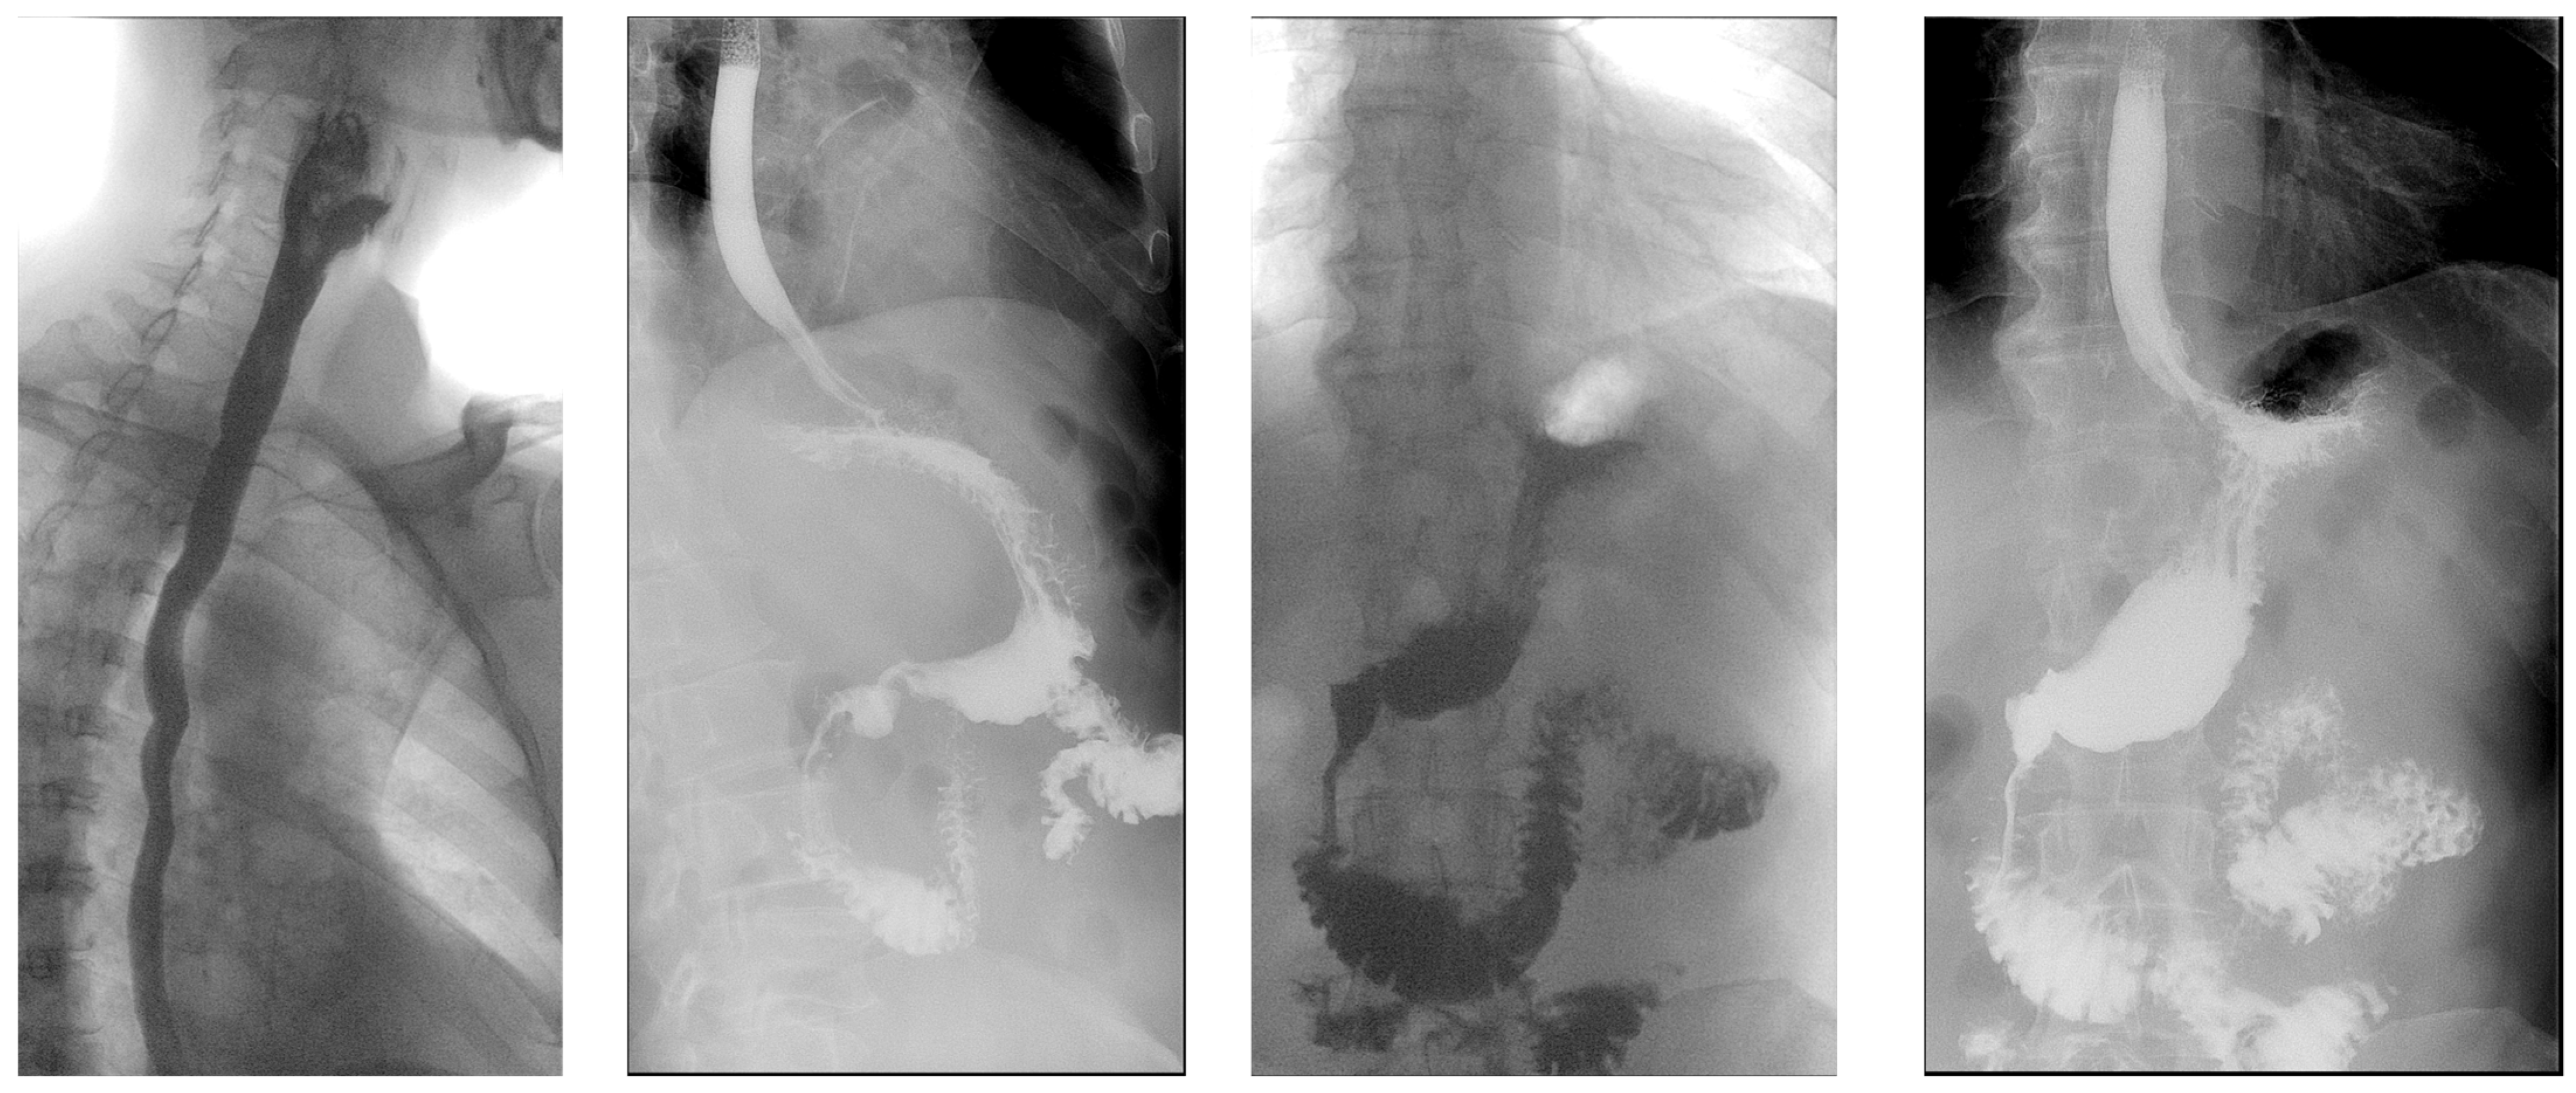

2. Case